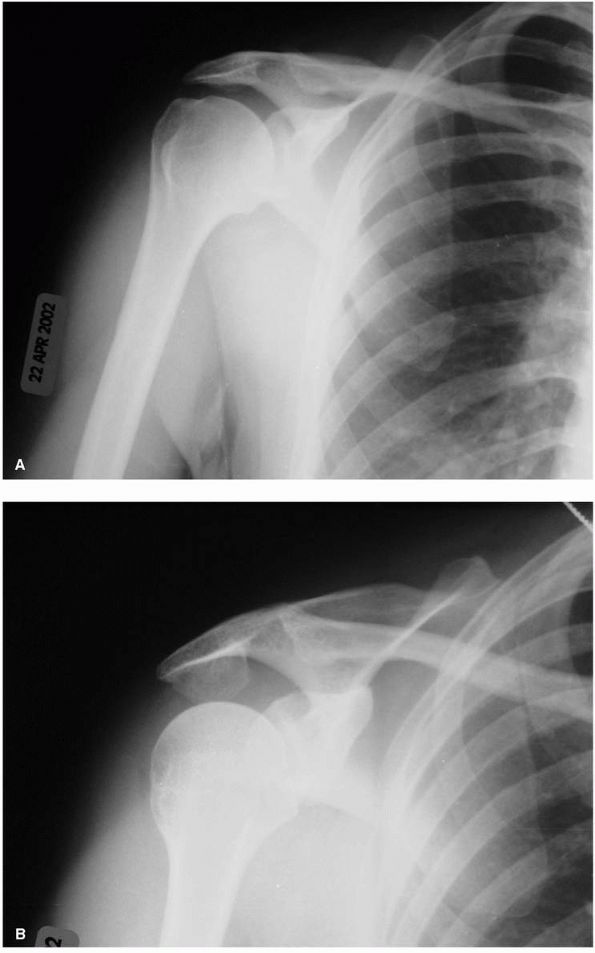

![]() |

FIGURE 12-7. Glenohumeral osteoarthritis. (A) Anteroposterior radiograph demonstrating joint space narrowing (large black arrow), osteophyte formation (large white arrows), and subchondral cysts (small black arrows). (B) Axillary view showing typical posterior glenoid wear (large black arrows)

and posterior subluxation of the humeral head. The small black arrows indicate normal points of contact between the head and the glenoid. |

preoperative planning. The AP view is useful in determining the amount

of medial glenoid bone loss. Posterior glenoid bone erosion is common

and is best visualized on the axillary view. The

combination

provides crucial information in predicting the ability to resurface the

glenoid. Although not routine in the initial workup of primary

osteoarthritis, an MRI, usually obtained to determine the status of the

rotator cuff, or CT, may also yield additional information about

glenoid alignment and bone quantity (Figure 12-8).